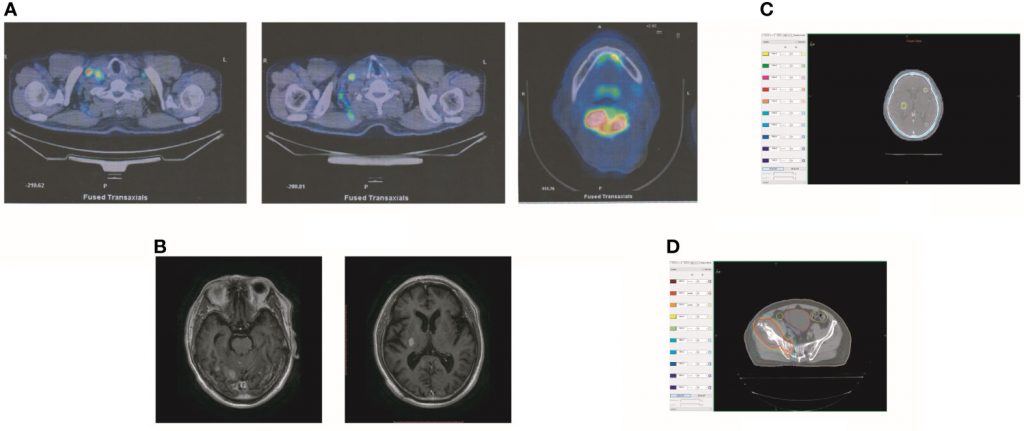

2019年10月,患者出现头晕、右髋疼痛。PET显示右侧髂骨和右侧坐骨多发骨转移(图2A)。此外,大脑中有多个转移灶(图2A)。对比增强磁共振成像(MRI)揭示了九个BM(图2B)。实验室分析显示CEA水平为3.6。我们建议对右侧髂骨进行活检。由于患者颅内压高,头晕加重,他和家人拒绝活检。在通过NGS检查的血液样本中未检测到ALKr 。继刘的报告,患者接受了针对转移灶的全脑放疗(WBRT)联合同步综合强化(SIB)。WBRT的剂量为39.6Gy,分22次给药,SIB的剂量为55Gy,分22次给药(图2C)。患者还接受了右侧髂骨病变的放射治疗(60Gy,24个疗程,图2D)。尽管放疗使患者的右侧髋部疼痛有所改善,但他的颅内压却恶化了。该患者在完成10次颅内放疗后接受了MRI。MRI显示BM的数量增加到大约50(图3A)。经过慎重考虑,我们决定完成WBRT。完成WBRT后,患者昏迷,MRI显示大约80个BM,包括脑干中的一些(图3B)。据报道,根据组织学和配对液基细胞学标本之间的免疫染色,ALK状态的总体一致率为100%。然而,孤立性中枢神经系统(CNS)进展患者的基因组改变检出率较低。由于血液检测结果值得怀疑,患者每天两次接受艾乐替尼Alecensa(Alectinib)600mg。口服艾乐替尼Alecensa(Alectinib)一周后,患者意识逐渐恢复,一个月后身体症状也逐渐好转。MRI显示BM数量减少至约60个,转移肿瘤总体积减少(图4A))。一些转移灶消失了,尤其是在脑干中。然而,由于患者自主终止降压治疗,右侧丘脑出血并破裂入脑室,导致脑出血。患者因脑出血接受治疗。同时,患者继续服用艾乐替尼Alecensa(Alectinib)。出现出血后经过一个月的治疗,患者的病情逐渐稳定。MRI显示大部分血肿被吸收,BMs数量进一步减少至约20个(图4B)。总转移性肿瘤体积也进一步减少。

图2

图2克唑替尼治疗后肿瘤复发。(A) PET显示右侧髂骨和右侧坐骨多发骨转移。此外,大脑中有多个转移灶。(B)对比MR显示患者有BM。(C) BM中放疗的剂量分布。(D)放疗在右侧髂骨病变中的剂量分布。